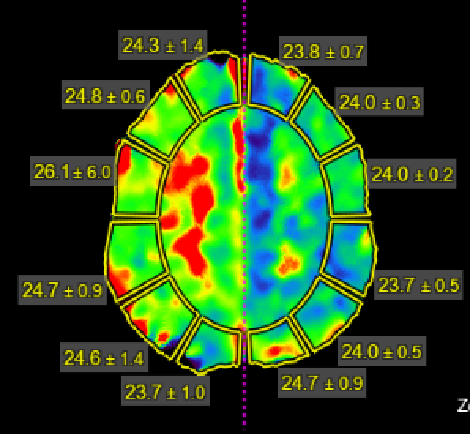

老人家进入医院全面评估后,发现右侧颅内一个主血管存在多节段局限性卡脖子的狭窄,TTP较对侧明显延长,呈缺血状态………,医院多学科讨论评估后,给予第一次外科干预后,患者瘫痪的肢体活动有改善,家人很开心……;在第二次干预之前,又出现了小的新发脑梗塞,继续药物保守治疗,可能还会梗塞;外科干预吧,刚刚出现新发的梗塞,出血风险大,况且又是高龄老年人,血管条件都是个未知数………。本来计划好的二期干预方案受到挑战,面对两难尴尬境地,所有的家人都一时难以决定:向左走?向右走?还是原地踏步进行观望?